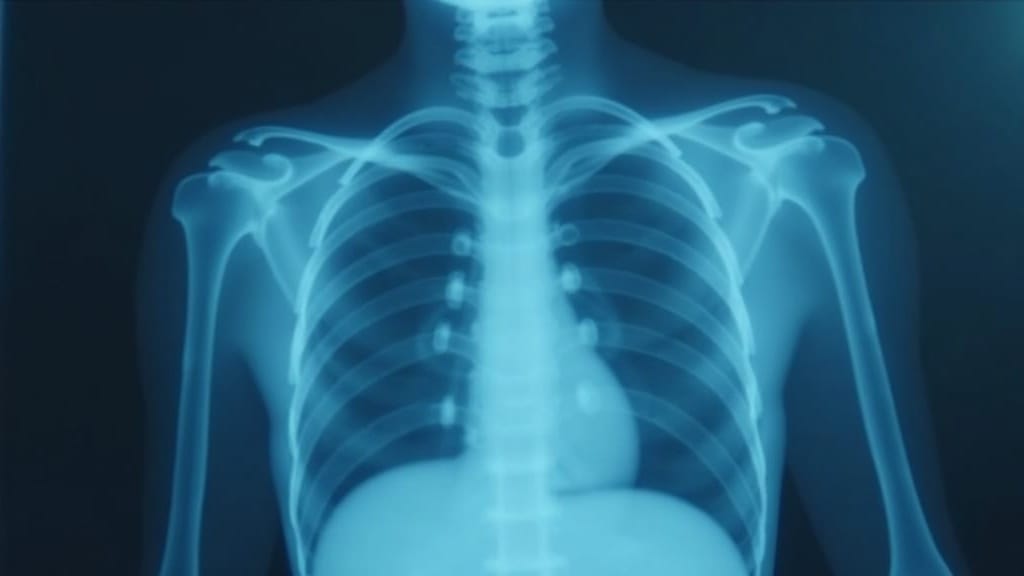

After nearly a century without significant advancement, tuberculosis vaccine development has reached a watershed moment. The M72/AS01E vaccine candidate has demonstrated approximately 50% efficacy against pulmonary TB in adults with latent M. tuberculosis infection — a result that could save millions of lives if confirmed in larger trials.

The significance cannot be overstated. Tuberculosis kills more people than any other infectious disease, including HIV/AIDS and malaria. The existing BCG vaccine, developed over 100 years ago, provides limited protection in adults — precisely the population most at risk of developing active, transmissible disease. A vaccine that prevents pulmonary TB in adults would transform global health.

The 50% efficacy figure, reported from a Phase 2b trial, exceeds the threshold many experts considered necessary for a viable TB vaccine. It suggests that the immune system can be trained to recognize and combat M. tuberculosis before it establishes active infection — something the BCG vaccine largely fails to do in adults.